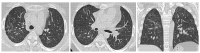

Polymyositis and dermatomyositis are autoimmune idiopathic systemic inflammatory diseases, characterized by various degrees of muscle inflammation and typical cutaneous lesions-the latter found in dermatomyositis. The underlying pathogenesis is characterized by a high level of uncertainty, and recent studies suggest diseases may have different immunopathological mechanisms. In polymyositis, components of the cellular immune system are involved, whereas in dermatomyositis, the pathogenesis is mainly mediated by the humoral immune response. The interstitial lung disease occurs in one-third of polymyositis and dermatomyositis patients associated with worse outcomes, showing an estimated excess mortality rate of around 40%. Lung involvement may also appear, such as a complication of muscle weakness, mainly represented by aspiration pneumonia or respiratory insufficiency. The clinical picture is characterized, in most cases, by progressive dyspnea and non-productive cough. In some cases, hemoptysis and chest pain are found. Onset can be acute, sub-acute, or chronic. Pulmonary involvement could be assessed by High Resolution Computed Tomography (HRCT), which may identify early manifestations of diseases. Moreover, Computed Tomography (CT) appearances can be highly variable depending on the positivity of myositis-specific autoantibodies. The most common pathological patterns include fibrotic and cellular nonspecific interstitial pneumonia or organizing pneumonia; major findings observed on HRCT images are represented by consolidations, ground-glass opacities, and reticulations. Other findings include honeycombing, subpleural bands, and traction bronchiectasis. In patients having Anti-ARS Abs, HRCT features may develop with consolidations, ground glass opacities (GGOs), and reticular opacities in the peripheral portions; nonspecific interstitial pneumonia or nonspecific interstitial pneumonia mixed with organizing pneumonia have been reported as the most frequently encountered patterns. In patients with anti-MDA5 Abs, mixed or unclassifiable patterns are frequently observed at imaging. HRCT is a sensitive method that allows one not only to identify disease, but also to monitor the effectiveness of treatment and detect disease progression and/or complications; however, radiological findings are not specific. Therefore, aim of this pictorial essay is to describe clinical and radiological features of interstitial lung diseases associated with polymyositis and dermatomyositis, emphasizing the concept that gold standard for diagnosis and classification-should be based on a multidisciplinary approach.